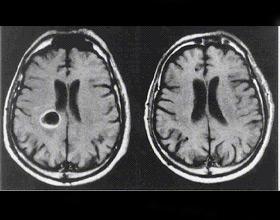

En los ambientes del Instituto de Investigación Biomédica de Bellvitge (Cataluña, España), un grupo de científicos ha descubierto una molécula que frena el desarrollo de tumores cerebrales, según informaron este martes en un comunicado.

La molécula, de nombre Nutlina-3a, activa una proteína que induce muerte celular y pérdida de capacidad para reproducirse del cáncer, tal y como destacan los resultados de esta investigación.

Avelina Tortosa, coordinadora del estudio, explicó que uno de los objetivos del grupo es sensibilizar las células cerebrales para que la radioterapia sea más efecvtiva.

"La radioterapia induce daños en el ADN de las células tumorales", recordó Tortosa.

Asimismo, la investigadora precisó que con la Nutlina-3a aumenta la muerte de células tumorales "y por lo tanto aumenta la eficacia del tratamiento de radioterapia". (Con información de EFE)